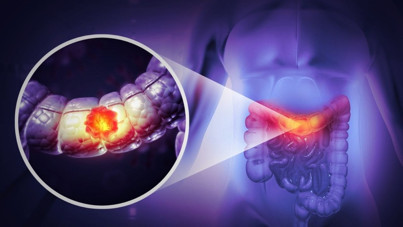

Bilim insanları buldu: İşte kolon kanseri riskini artıran bu genmiş Bilim insanları genç insanlarda kolon kanserini tetikleyen bir gen tespit etti. Bu geni devre dışı bırakmanın kolon kanserini küçülttüğü ve farelerin hayatta kalma süresini artırdığı görüldü.